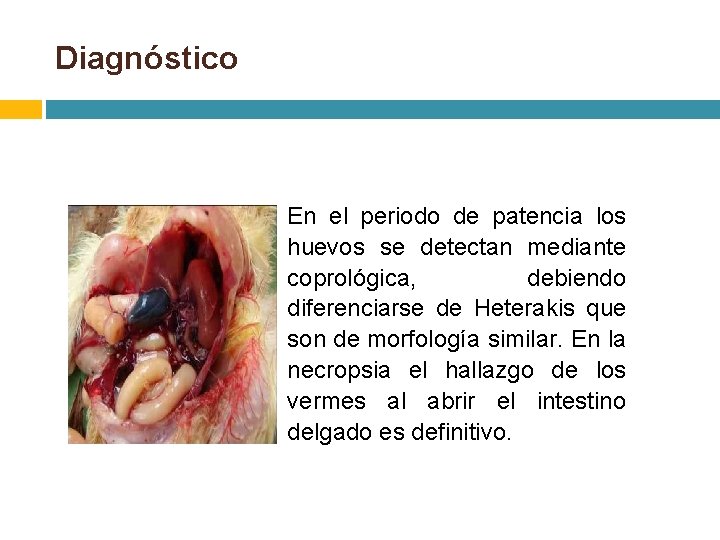

Diagnóstico En el periodo de patencia los huevos se detectan mediante coprológica, debiendo diferenciarse de Heterakis que son de morfología similar. En la necropsia el hallazgo de los vermes al abrir el intestino delgado es definitivo.